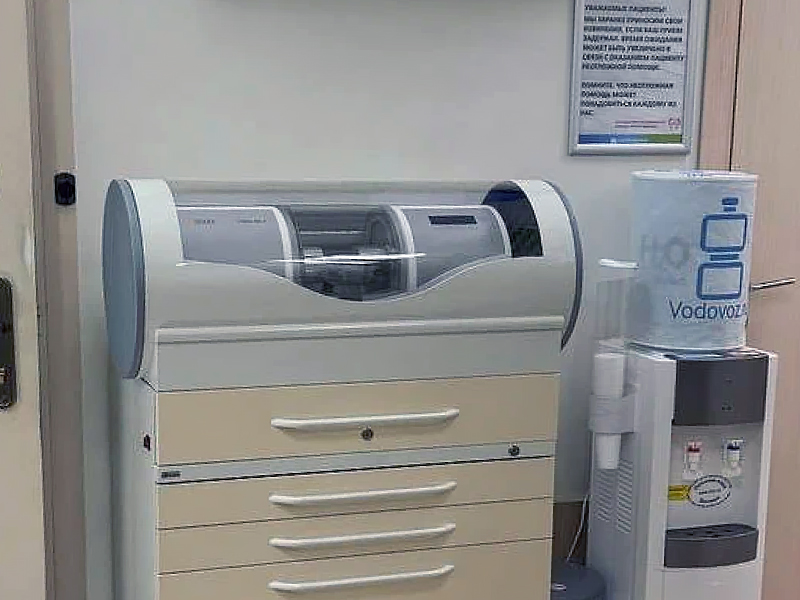

Применяемое оборудование

ДКТ - (Дентальная компьютерная томография)

ДКТ (пациенту из другого ЛПУ)

8930

ДКТ (по направлению нашей клиники)

4254